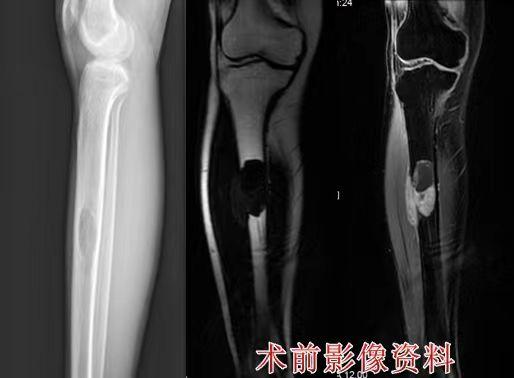

52143672_273d8b75-306e-4014-9709-aaa47f08e023.jpg

小敏(化名)术前影像资料 受访者供图

日前,14岁的小敏(化名)因左膝酸痛前往 就诊,经详细检查后被明确诊断为骨肉瘤。

对于一个14岁的花季少女来说,如果进行“截肢”无异于噩耗。因此,医院骨肉瘤MDT团队经讨论后决定先进行术前新辅助化疗,术前共进行3程新辅助化疗,过程顺利,化疗后肿瘤体积较化疗前缩小,边界清晰。考虑到年轻患者生存期较长,正常骨骼还会继续生长发育,术前讨论决定采用左股骨远端骨肉瘤广泛切+定制人工肿瘤膝关节重建。